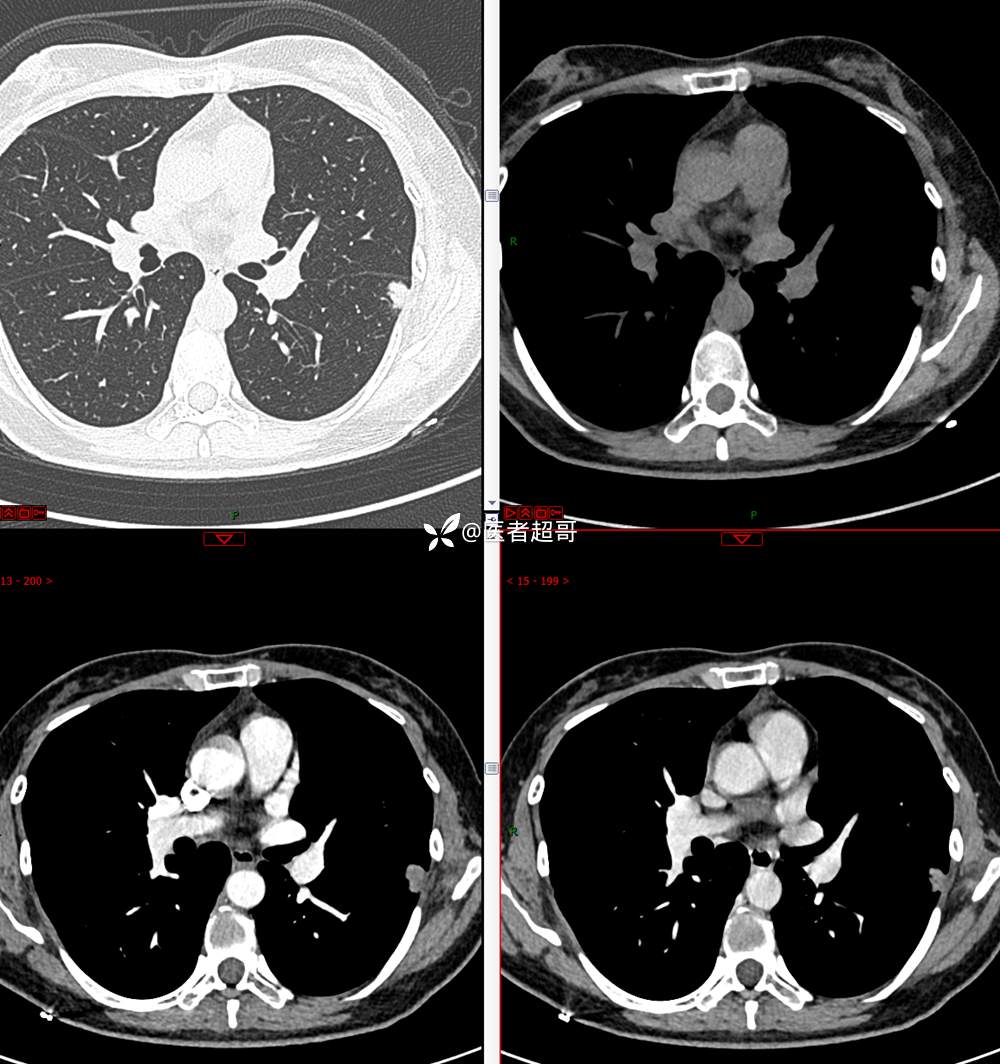

【影诊笔记705】查体发现肺肿物2月余,请诊断分析~~~

主 诉:查体发现肺肿物2月余

现病史:患者于2月余前行X线及胸部CT示:左肺结节。当时患者无明显不适,行抗炎治疗后复诊。于我院查胸部(肺)CT平扫示:左肺下叶实性小结节,请结合临床及原片,必要时进一步检查;双肺钙化灶右肺上叶微结节,建议随诊肝内钙化灶,门诊以“肺肿物”收入院。患者自发病以来,咳嗽咳痰,无痰中带血,无咯血,无胸闷胸痛,无心慌气短,无发热盗汗、无全身乏力,无头痛头晕,无恶心呕吐,无腹痛腹胀,无声音嘶哑及呛咳。患者自发病以来,神志清,精神可,饮食可,睡眠良好,大小便正常,近期体重未见明显增减。